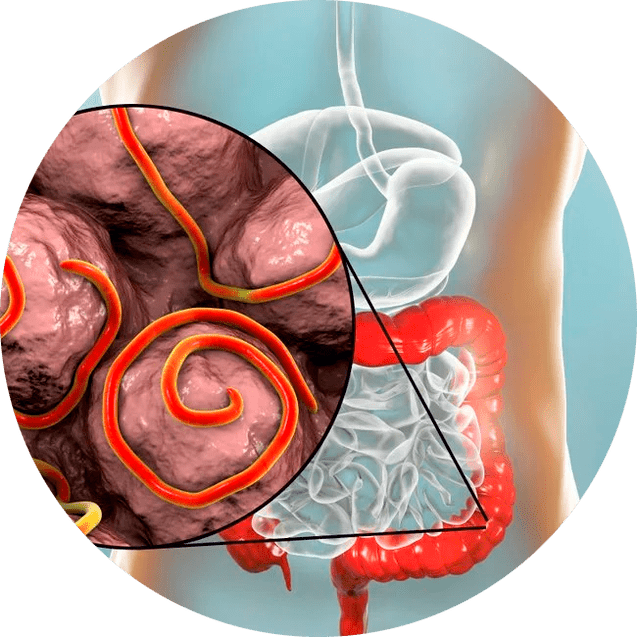

El medicamento actúa en varias direcciones simultáneamente:

- promueve la eliminación de gusanos y otros parásitos;

- normaliza el funcionamiento del tracto gastrointestinal, eliminando molestias y trastornos;

- restaura la microflora intestinal saludable;

- reduce la carga tóxica en el cuerpo;

- fortalece las funciones protectoras naturales del tracto gastrointestinal.

¿Cuándo se recomienda su uso? NEOflorax

El medicamento está indicado en los siguientes casos:

- si sospecha una infección por parásitos (gusanos, helmintos);

- para trastornos digestivos causados por trastornos de la microflora;

- para la prevención de infecciones parasitarias en condiciones de alto riesgo;

- con síntomas de disbacteriosis (hinchazón, diarrea, estreñimiento);

- durante el período de recuperación después del tratamiento con antibióticos.